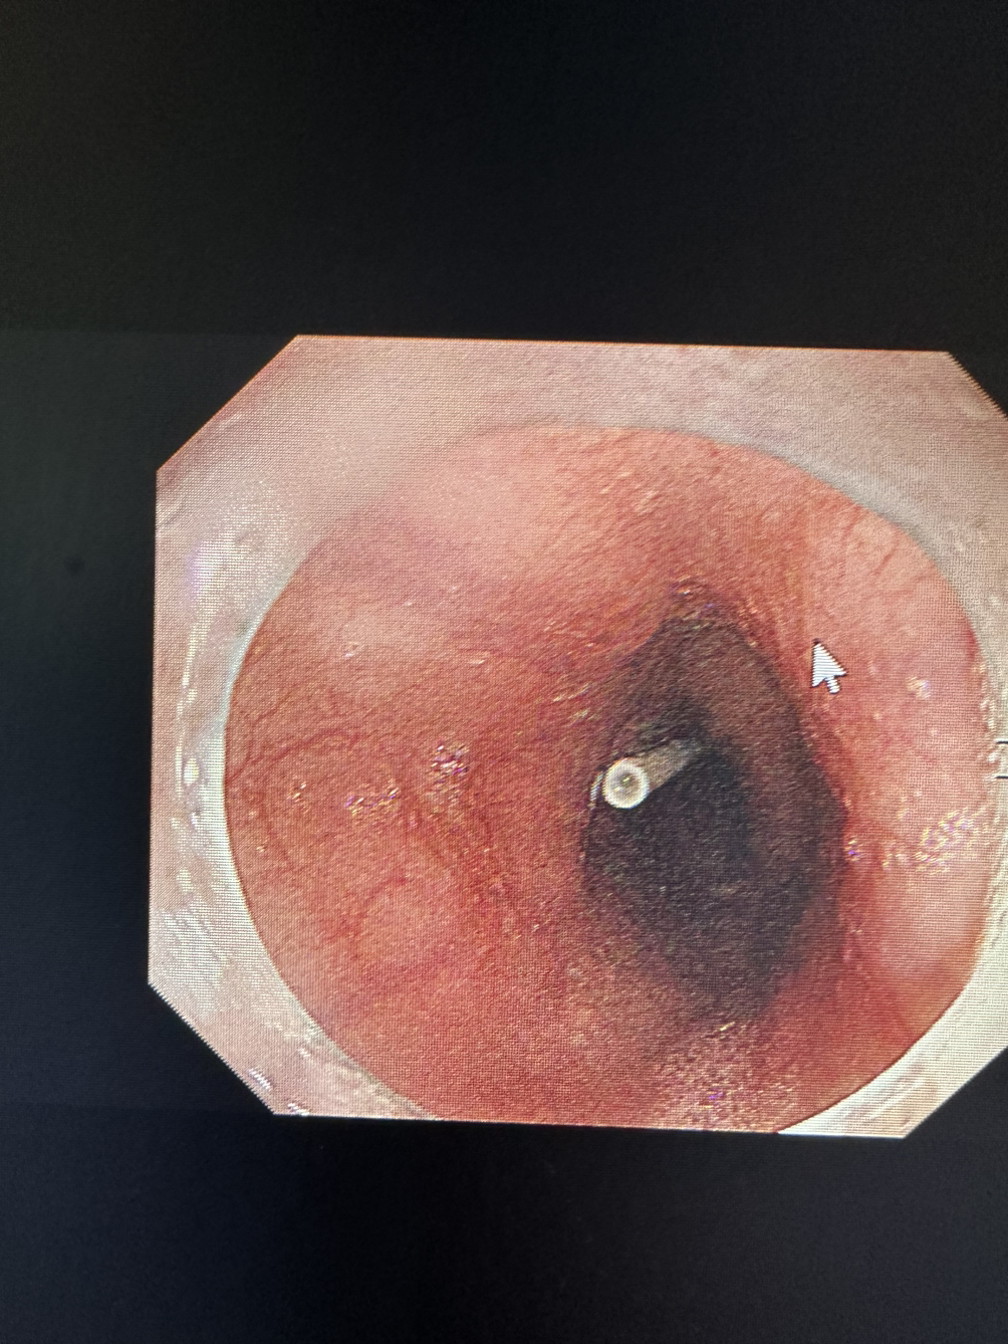

재소자들은 불가능에 도전한다. 칫솔도, 연필도, 뚜껑부터 해서 여러 가지를 삼키고 온다. 여러 가지 추론을 해볼 수 있겠지만 정확한 이유는 그들만이 알 거다. 그들은 여러 명의 교도관을 대동하고 죄수복(?)을 입고 온다. 자주 삼키는 사람도 있었고 수면으로 안 하면 이대로 죽겠다고 소리치는 사람도 있었다. 생의 의지는 생각보다 강하고 그들의 외침은 생존을 향한 몸부림이다. 이러한 이물을 제거하는 이는 정해져 있다. 주로 K교수님이 많이 하고 함께하는 간호사는 나다. 이유는 모른다.